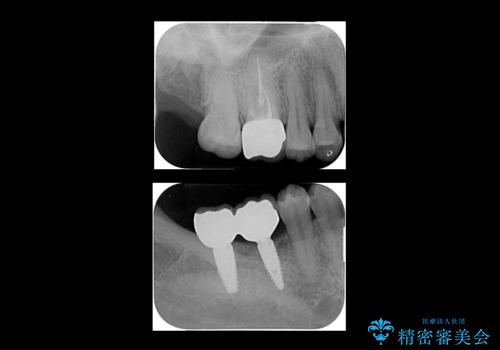

右下は虫歯がひどく、抜歯が必要でした。また、右下の一番奥の歯は親知らずのため使うことができない状態でした。

右上に部分矯正を行い、クリアランスを確保した後、右下にイプラントを2本埋入しています。

上の歯が伸びだしてきていたため、部分矯正を行い歯を移動させてから、向かい合わせの歯にインプラント治療を行っています。

右上第一大臼歯は六本木院の林院長に根管治療をお願いしました。